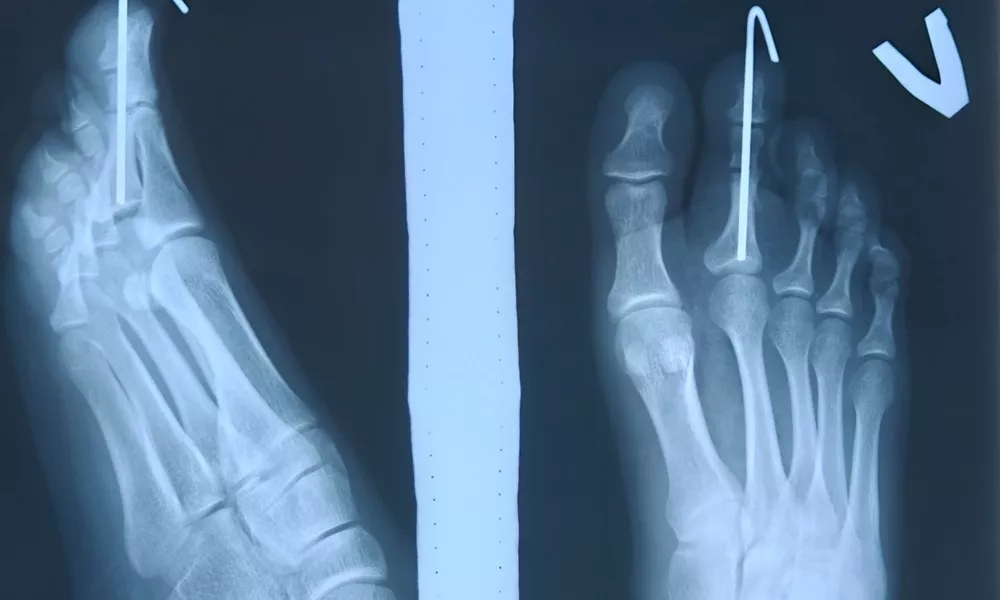

В ходе операции бригада врачей выполнила реконструкцию пальца: укоротили костную фалангу и зафиксировали ее специальной спицей, а также удалили лишние мягкие ткани. Весь процесс прошел успешно и медикам удалось сформировать эстетически правильный и подвижный палец. Пациентка выразила огромную благодарность специалистам за возможность вести комфортную жизнь.